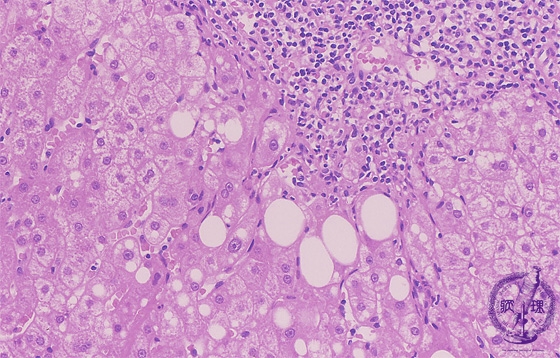

Microscopic image (HE stain, high power view): There is dense portal chronic inflammation with interface hepatitis comprising lymphocytic inflammation at the limiting plate and concurrent hepatocellular drop-out (yellow box). Hepatocytes contain large cytoplasmic lipid droplets (steatosis).